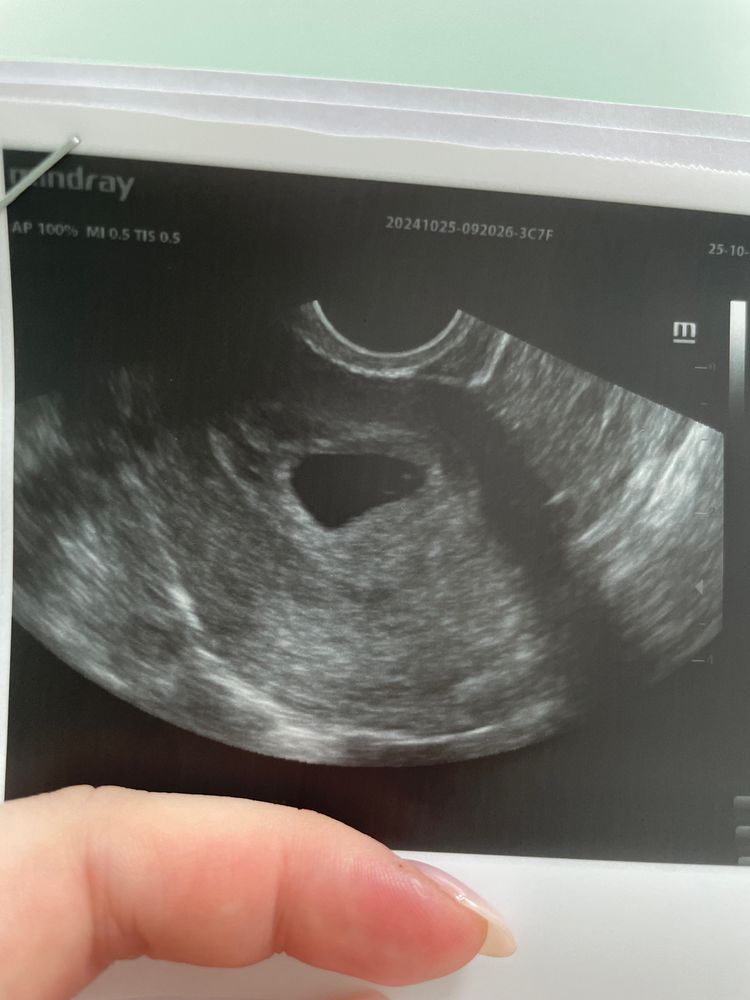

Первое УЗИ срок 6.1

25.10.2024